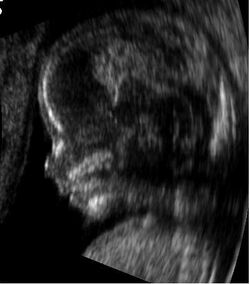

Ultrasound image (sonogram) of a fetus in the womb, viewed at 12 weeks of pregnancy (bidimensional scan)

Sonogram of a fetus at 14 weeks (profile)

The potential for ultrasonic imaging of objects, with a 3 GHz sound wave producing resolution comparable to an optical image, was recognized by Sokolov in 1939, but techniques of the time produced relatively low-contrast images with poor sensitivity.[27] Ultrasonic imaging uses frequencies of 2 megahertz and higher; the shorter wavelength allows resolution of small internal details in structures and tissues. The power density is generally less than 1 watt per square centimetre to avoid heating and cavitation effects in the object under examination.[28] High and ultra high ultrasound waves are used in acoustic microscopy, with frequencies up to 4 gigahertz. Ultrasonic imaging applications include industrial nondestructive testing, quality control and medical uses.[27]